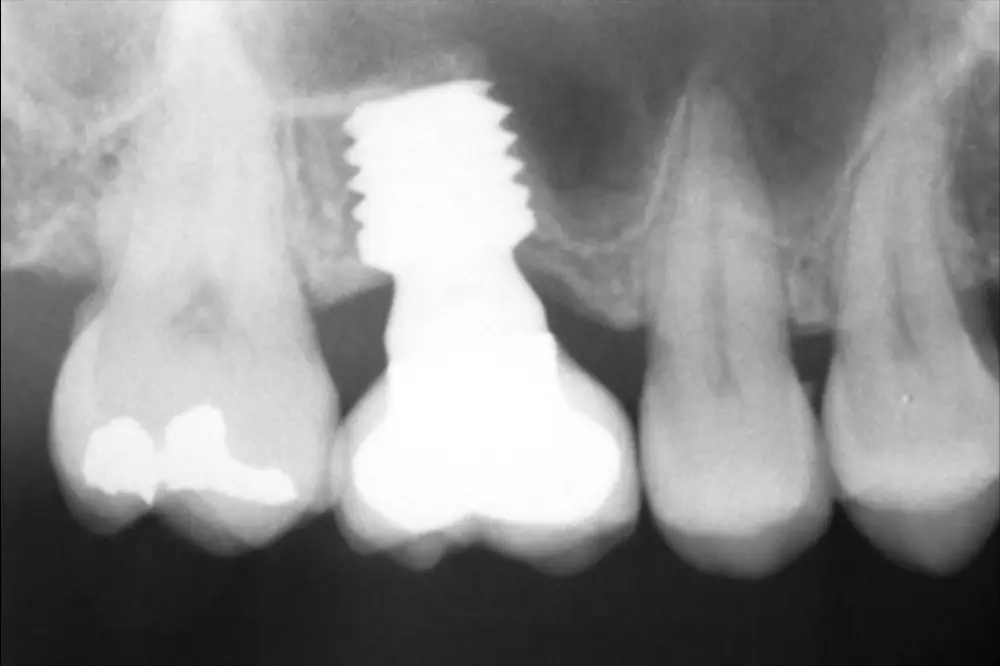

Fig. 7. Radiografía postquirúrgica con el implante en una fase con el pilar de cicatrización.

Fig. 8. Cone-beam de planificación donde observamos la escasa altura residual de la cresta a nivel de la pieza 16.